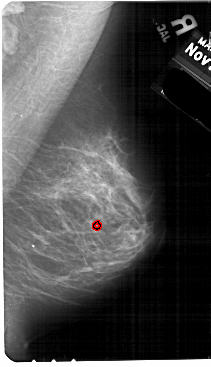

A_1614_1.LEFT_MLO

LEFT_MLO LINES 5491 PIXELS_PER_LINE 3256 BITS_PER_PIXEL 12 RESOLUTION 43.5 NON_OVERLAY

FILE: A_1614_1.RIGHT_MLO.OVERLAY

TOTAL_ABNORMALITIES 1

ABNORMALITY 1

LESION_TYPE CALCIFICATION TYPE PLEOMORPHIC DISTRIBUTION CLUSTERED

ASSESSMENT 4

SUBTLETY 1

PATHOLOGY MALIGNANT

TOTAL_OUTLINES 1

BOUNDARY